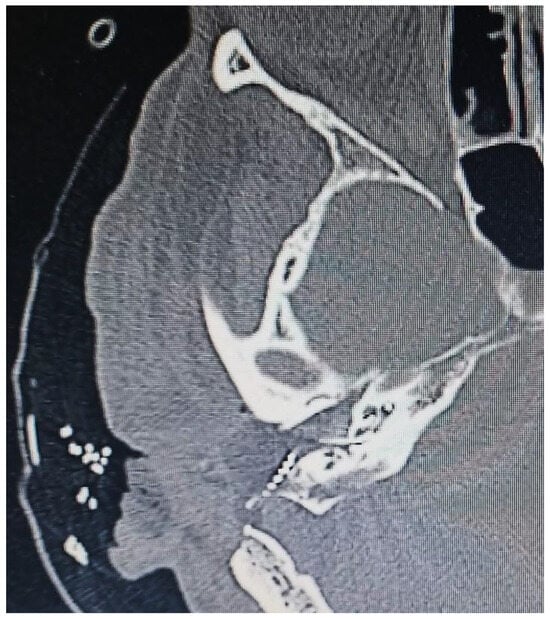

Middle Ear Cholesteatoma and Vestibular Schwannoma Resection Followed by Cochlear Implant: Surgical Challenges and Audiological Outcomes

2. Case Report